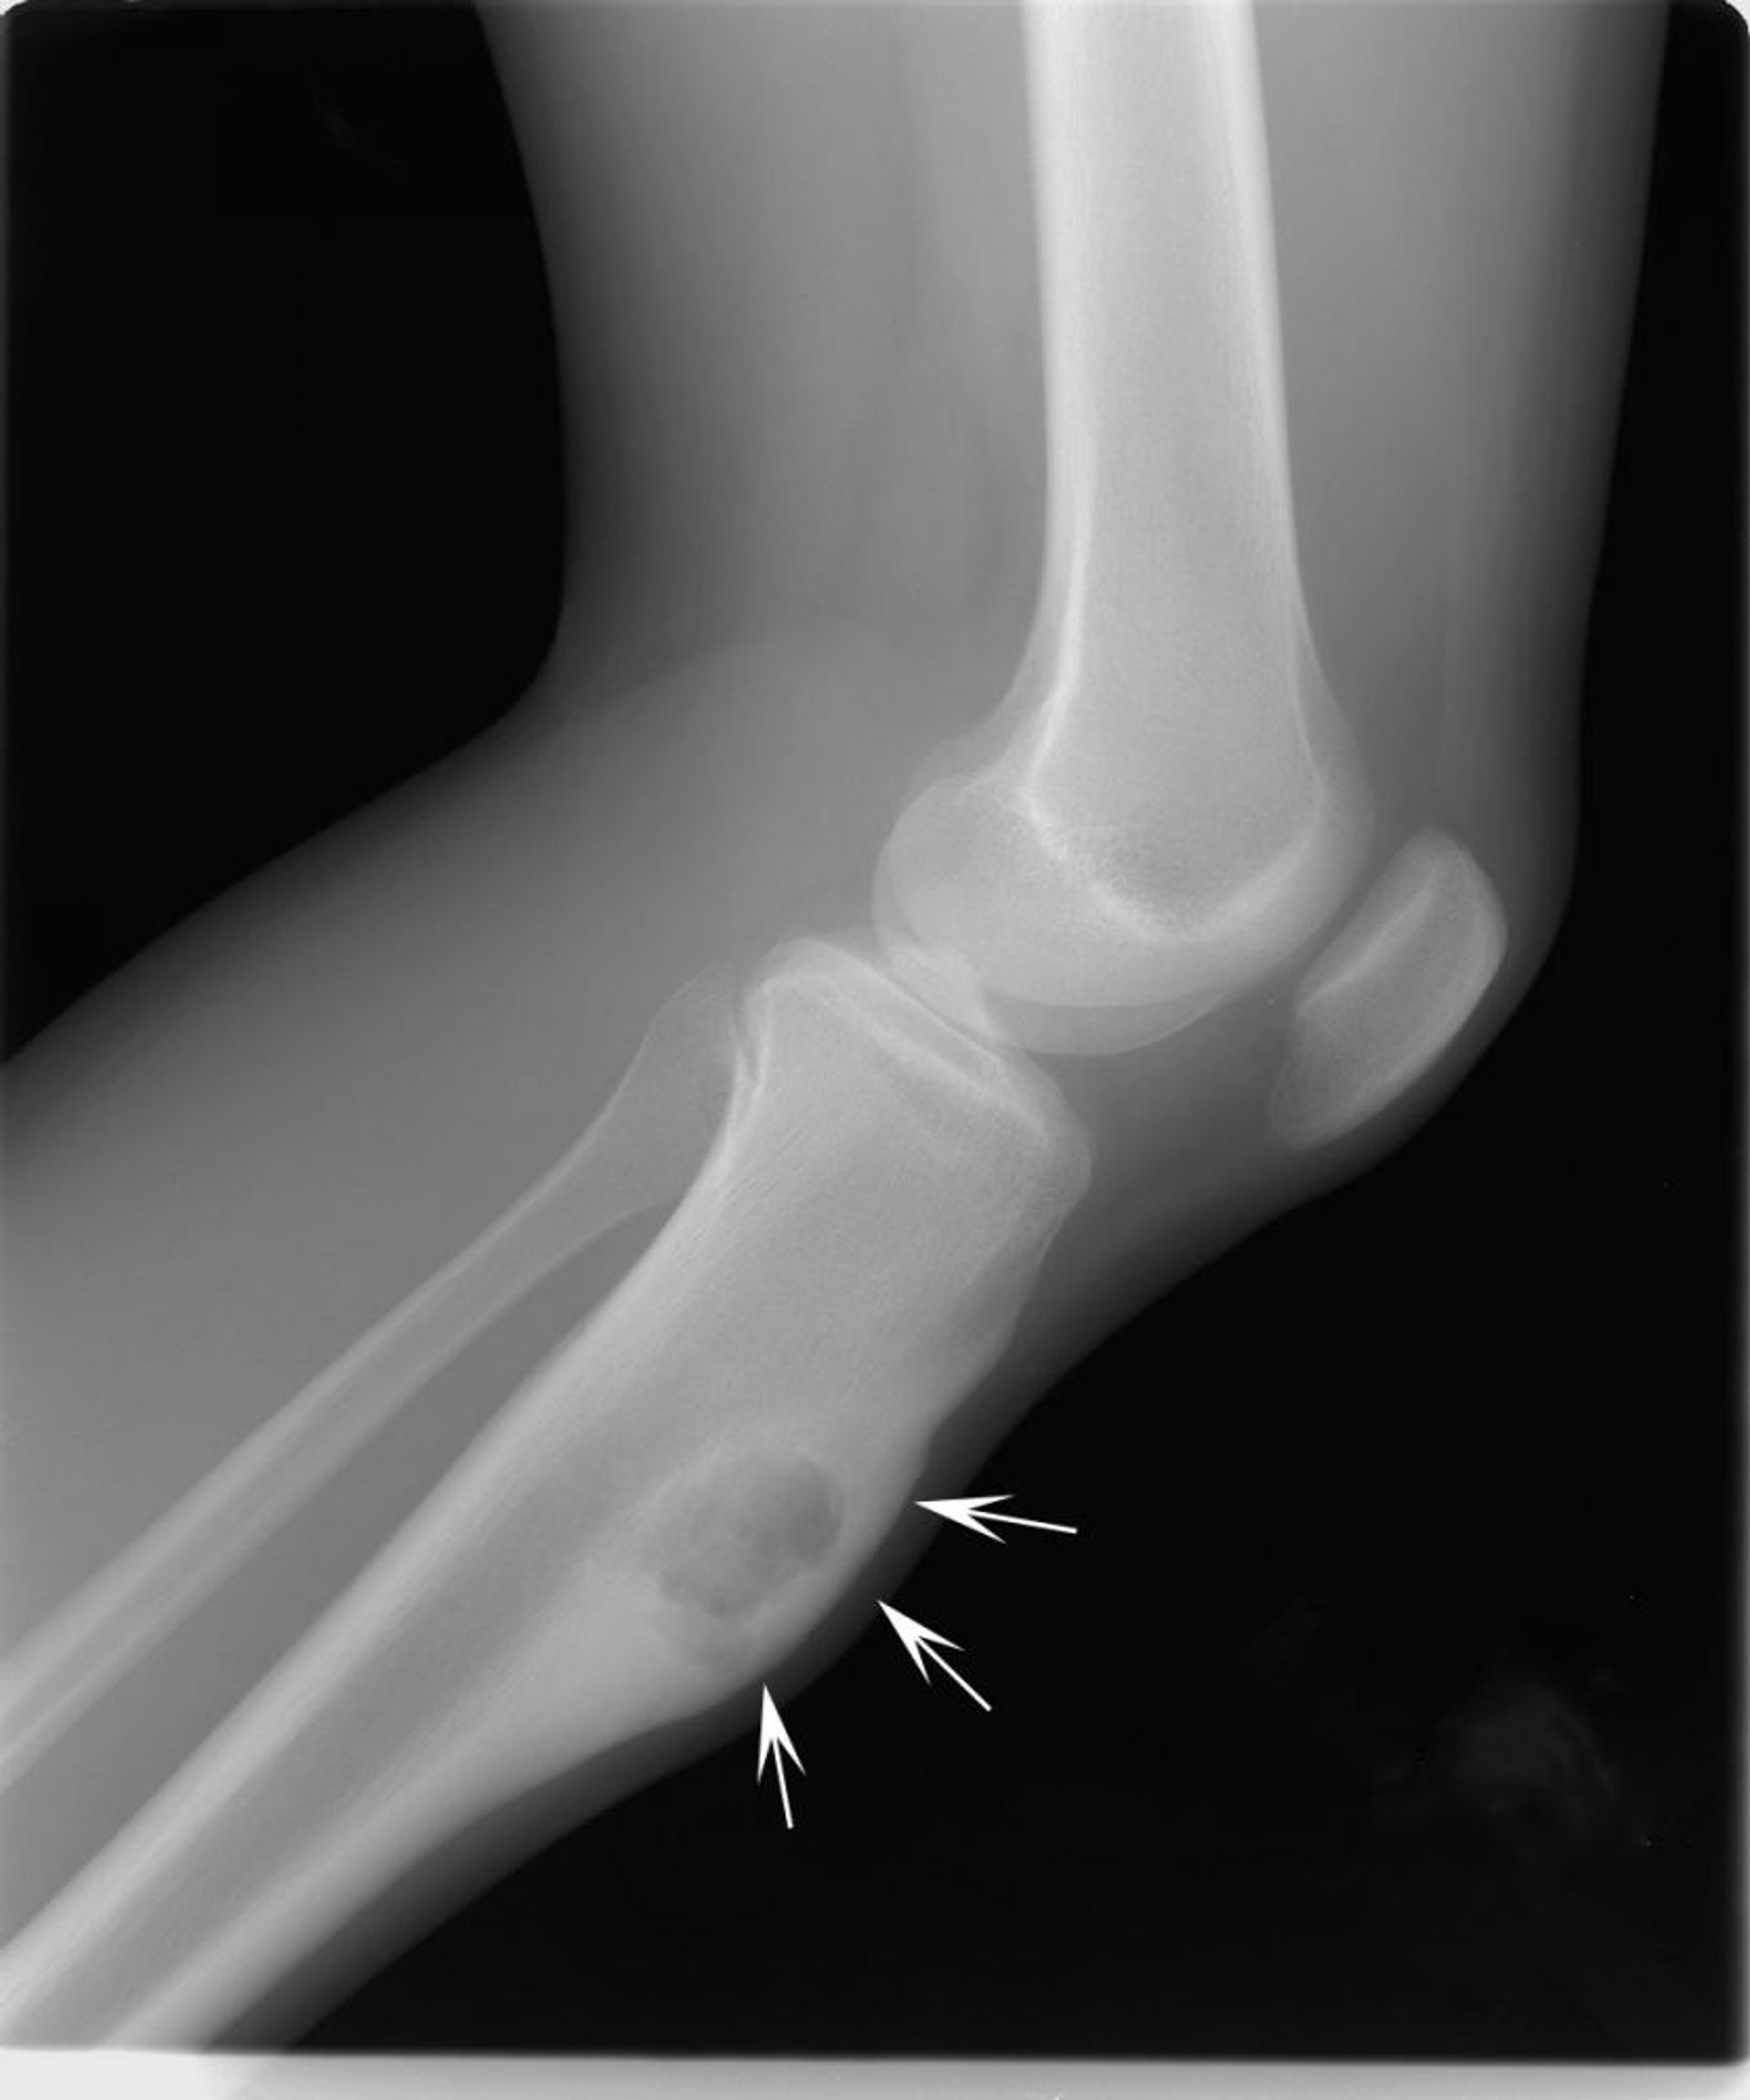

На данном рентгеновском снимке колена показана хондромиксоидная фиброма в большеберцовой кости ниже колена (стрелки), расширяющая кость в передней части.

Image courtesy of Michael J. Joyce, MD, and Hakan Ilaslan, MD.